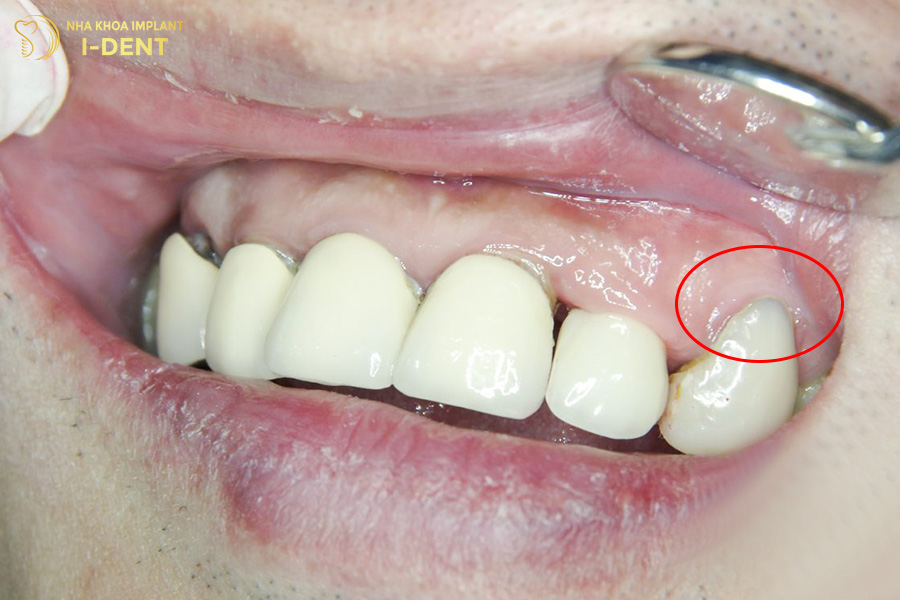

1.1. Xuất hiện khe hở giữa răng sứ và nướu

Dấu hiệu điển hình của dấu hiệu răng sứ bị hở là có một khe hở ở vùng tiếp giáp giữa răng sứ và nướu khi nhìn qua gương hoặc cảm nhận bằng lưỡi.

Khe hở này tạo điều kiện cho mảng bám, vi khuẩn tích tụ, từ đó gây ra đau nhức, viêm nhiễm và làm tổn hại phần cùi răng thật bên trong. Điều này có thể khiến răng thật mất chức năng nâng đỡ mão sứ, dẫn đến dễ gãy hoặc rụng răng.

Khe hở giữa vùng chân răng sứ và nướu có thể quan sát bằng mắt thường hoặc dùng lưỡi cảm nhận